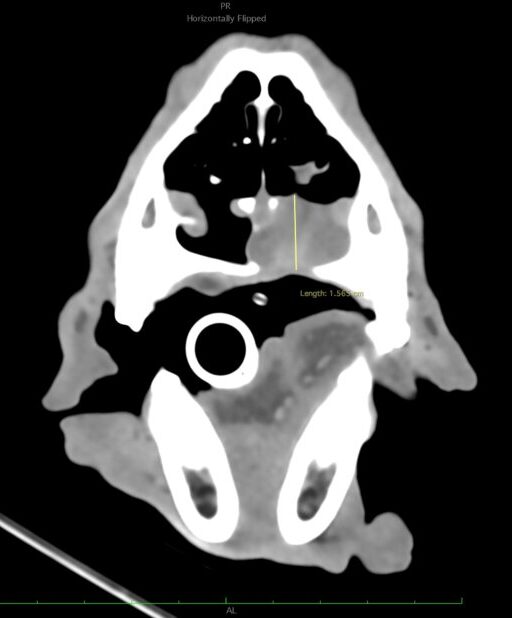

A los 18 meses del diagnóstico, los cuidadores refieren la aparición de hifema y exoftalmia en el ojo derecho, lo que sugiere metástasis, además de una masa perianal compatible con neoplasia indiferenciada (posible melanoma amelanótico). En el estudio de TC se documenta una respuesta completa de la lesión primaria y metástasis nodales y una remisión casi completa de las metástasis pulmonares (lesiones milimétricas equívocas) (imagen 1). Se realiza la resección de la masa perianal, pero los cuidadores rechazan la enucleación.

A los 28 meses se realiza un TC de re-estadiaje antes de considerar el segundo protocolo de radioterapia, donde se documenta una progresión objetiva de la masa oral y ligera progresión de la metástasis pulmonar (imagen 1).